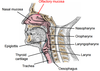

Identify some key anatomical features on the larynx diagram below:

Identify the 7 components of the conducting portion of the respiratory tract

- Nasal cavity

- Pharynx

- Larynx

- Trachea

- Primary bronchi

- Secondary bronchi

- Bronchioles

- Terminal bronchioles